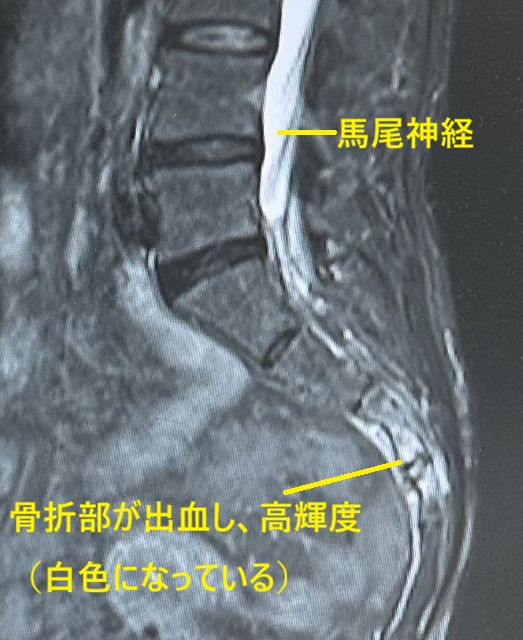

うつ伏せにして、仙骨部や尾骨部を圧迫すると飛び上がるような痛みを訴えます。時に仙骨骨折は神経損傷(足の感覚障害や筋力低下)や尿路障害などの合併症を訴えることもありますので要注意です。診断はレントゲン検査(仙骨骨折尾骨骨折尾骨亜脱臼)で容易に判断できます。時に経過中に転位されて(ずれて)症状が長引く症例を経験します。